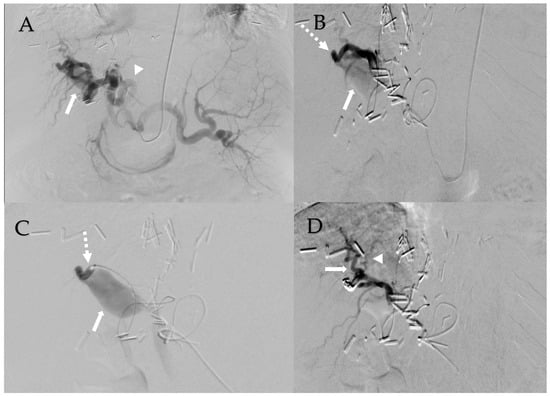

Given the extensive nature of the HAPVF and his hepatic decompensation, the decision was made to treat the fistula with transcatheter embolization. His pre-operative lab work included a creatinine of 1.6 mg/dL, total bilirubin 1.48 mg/dL, platelets 51,000, and INR 1.35. Celiac arteriography revealed a dilated and extremely long and tortuous common and proper hepatic artery (Figure 2A). Hepatic arteriograms demonstrated a short-segment fistula between the right hepatic artery and the portal vein (Figure 2B,C). Close and central to the fistula were two significant branches of the right hepatic artery. Attempts were made to deploy a vascular plug into the fistula without success because the delivery sheath could not track along the tortuous hepatic artery. The initial placement of detachable coils resulted in unconstrained extension into the main portal vein, requiring their removal before deployment. Finally, detachable coils were deployed into the short-segment fistula (one Concerto 2 mm and one Concerto 8 mm coil). A post-embolization arteriogram showed occlusion of the HAPVF without injury to the two adjacent normal right hepatic arteries (Figure 2D). His bilirubin decreased from 1.48 to 1.02 mg/dL. Post-procedure MRI found successful closure of the HAPVF with patent hepatic arteries and portal vein without early enhancement, but rather with occlusion of the main, left, and right portal veins. There were periportal collaterals suggesting cavernous transformation. We presume that the hepatic artery had been providing retrograde flow into the portal system, which subsequently thrombosed after fistula closure. The splenic vein and superior mesenteric vein remained patent. A CT scan with contrast performed 4 years after embolization shows persisting portal vein thrombosis and the collateralization of portal venous inflow (Figure 3).

Figure 2. Management of hepatic arterio-portal venous fistula. (A): Celiac axis arteriogram shows hypertrophied and tortuous common/proper hepatic arteries (arrowhead) and bulbous portal vein (arrow). (B): Right hepatic artery arteriogram shows tortuous hepatic arteries with short-segment hepatic artery fistula (dashed arrow) with immediate opacification of the portal vein (arrow). (C): Right hepatic artery arteriogram shows short-segment hepatic artery fistula (dashed arrow) with immediate opacification of the portal vein (arrow). (D): Right hepatic artery arteriogram status post coil embolization of short-segment fistula shows two adjacent right hepatic arteries that remain patent (arrow, arrowhead). Portal vein is no longer appreciated.